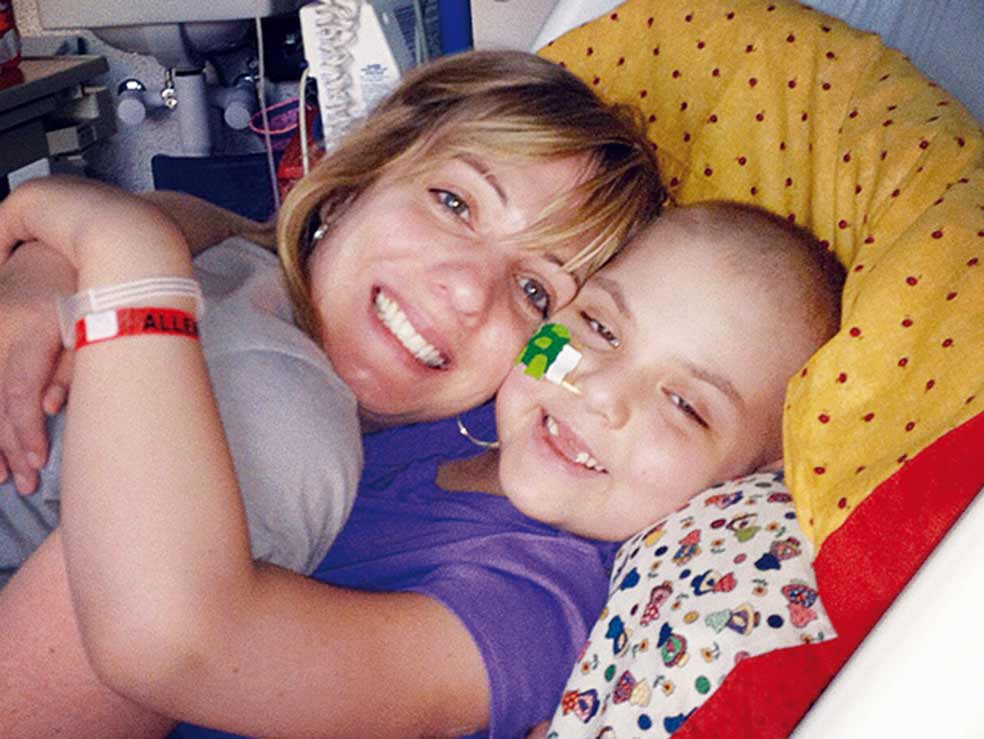

Padece leucemia», le dijo el médico a Kari Whitehead una mañana de mayo de 2010. «Ok», le contestó ella sin saber muy bien qué decir. Llevaba días sospechándolo. Su hija, Emma, de cinco años, sufría dolores, tenía el cuerpo salpicado de hematomas y

Padece leucemia», le dijo el médico a Kari Whitehead una mañana de mayo de 2010. «Ok», le contestó ella sin saber muy bien qué decir. Llevaba días sospechándolo. Su hija, Emma, de cinco años, sufría dolores, tenía el cuerpo salpicado de hematomas y sus ganglios linfáticos estaban inflamados desde hacía varios días. Kari había buscado todas las explicaciones razonables: un catarro, los juegos en el patio del colegio, las trastadas típicas de una niña de su edad… Pero entonces recordó un artículo que había leído años atrás sobre la leucemia infantil. Todos los síntomas encajaban. Pensó que se había convertido en una de esas madres neuróticas y sobreprotectoras, pero llevó a la niña al médico. Aquella consulta confirmó sus sospechas. Fue el inicio del calvario de Emma, quien, sin entender muy bien por qué, cambió el colegio y los juegos por las sesiones de quimioterapia, las visitas a urgencias y unos interminables ingresos hospitalarios.

Eso estuvo a punto de costarle la vida a Emma. Ingresada en la unidad de cuidados intensivos y conectada a un respirador, el 24 de abril de 2012 los médicos anunciaban a sus padres que la niña tenía una probabilidad entre mil de sobrevivir a aquella noche. Familiares y amigos se acercaron al hospital para despedirse. «Puede que Emma no sobreviva a esta noche. Por favor, rezad para que su función pulmonar y renal mejore. Rezad porque no esté asustada y no sienta dolor», actualizaba un familiar en el blog.

El mismo mecanismo que estaba matando las células cancerígenas había provocado una respuesta inflamatoria exacerbada. Entonces, Carl June -jefe del equipo responsable del tratamiento- tuvo una epifanía. Su hija, enferma de artritis reumatoide, tomaba un fármaco capaz de detener la inflamación. En cuestión de horas, la fiebre de Emma bajó y su presión sanguínea volvió a ser normal. Tras una semana sedada, Emma despertó el día que cumplía siete años. Dos días después, sin poder aún hablar, logró componer un mensaje señalando una a una las letras. I'm happy (Estoy contenta).

«No hay células cancerígenas. ¡Las células CART funcionan!», escribía entusiasmada su madre después del primer análisis de sangre tras recibir el tratamiento. Diez años después Emma es una niña sana.